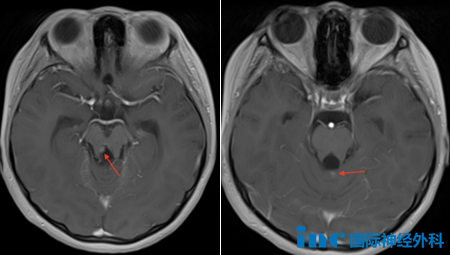

术后6个月随访复查时,影像学检查发现颅内出现多个小结节样病灶,位于小脑蚓部、右侧大脑脚及双侧脑室室管膜下区域。这些新发病灶引发肿瘤复发或转移的担忧,尽管初次手术已达到全切标准。

加拿大Rutka教授分析认为,右侧脑室周围和小脑蚓部的肿瘤结节可能为原发肿瘤残留病灶。若双侧侧脑室结节确实存在,则提示肿瘤转移可能性。目前这些小结节体积较小,部分在影像学上难以清晰显示,建议进行脊髓MRI检查以明确是否存在播散转移。